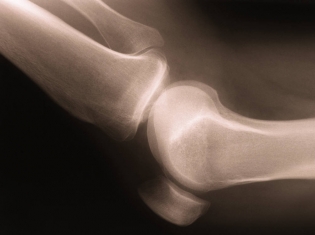

(RxWiki News) Some arthritis patients need surgery to repair severely damaged knees. You might think such surgery would bring relief only to the affected knee joints. But knee replacement surgery may offer even more benefits.

Elderly patients with osteoarthritis who undergo total knee replacement surgery may have a lower risk of heart failure and death.